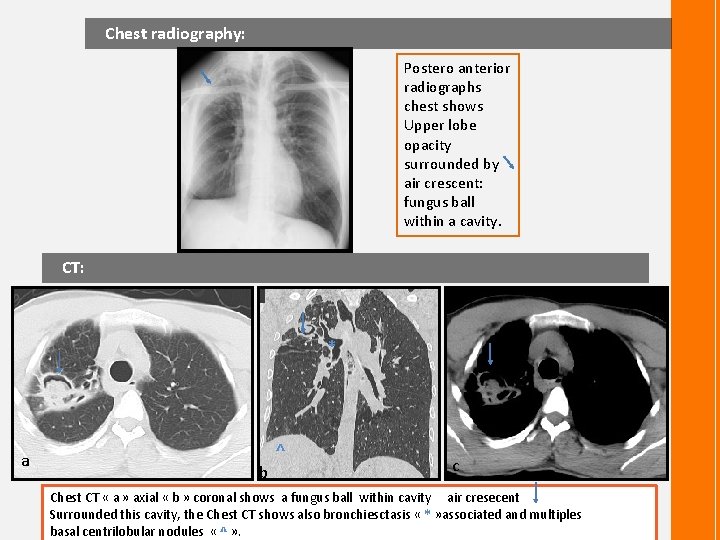

Chest radiography: Postero anterior radiographs chest shows Upper lobe opacity surrounded by air crescent: fungus ball within a cavity. CT: * a ^ b c Chest CT « a » axial « b » coronal shows a fungus ball within cavity air cresecent Surrounded this cavity, the Chest CT shows also bronchiesctasis « * » associated and multiples basal centrilobular nodules « ^ » .